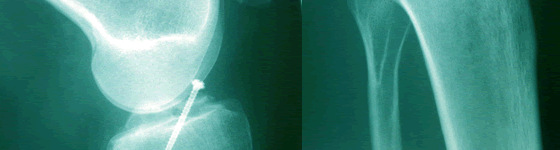

Darunter versteht man eine Zusammenfassung aller wichtigen, postoperativen Maßnahmen, wie Narbenpflege, Manueller Lymphdrainage zur Wundheilungsförderung, Manueller Therapie zur Wiederherstellung von optimaler Gelenk- und Muskelfunktion, Kräftigung der Muskulatur und gegebenenfalls das Erlernen der täglichen Alltags-Verrichtungen.

Die direkte postoperative Behandlung findet daher oft und besonders bei

älteren Menschen als Hausbesuch statt.